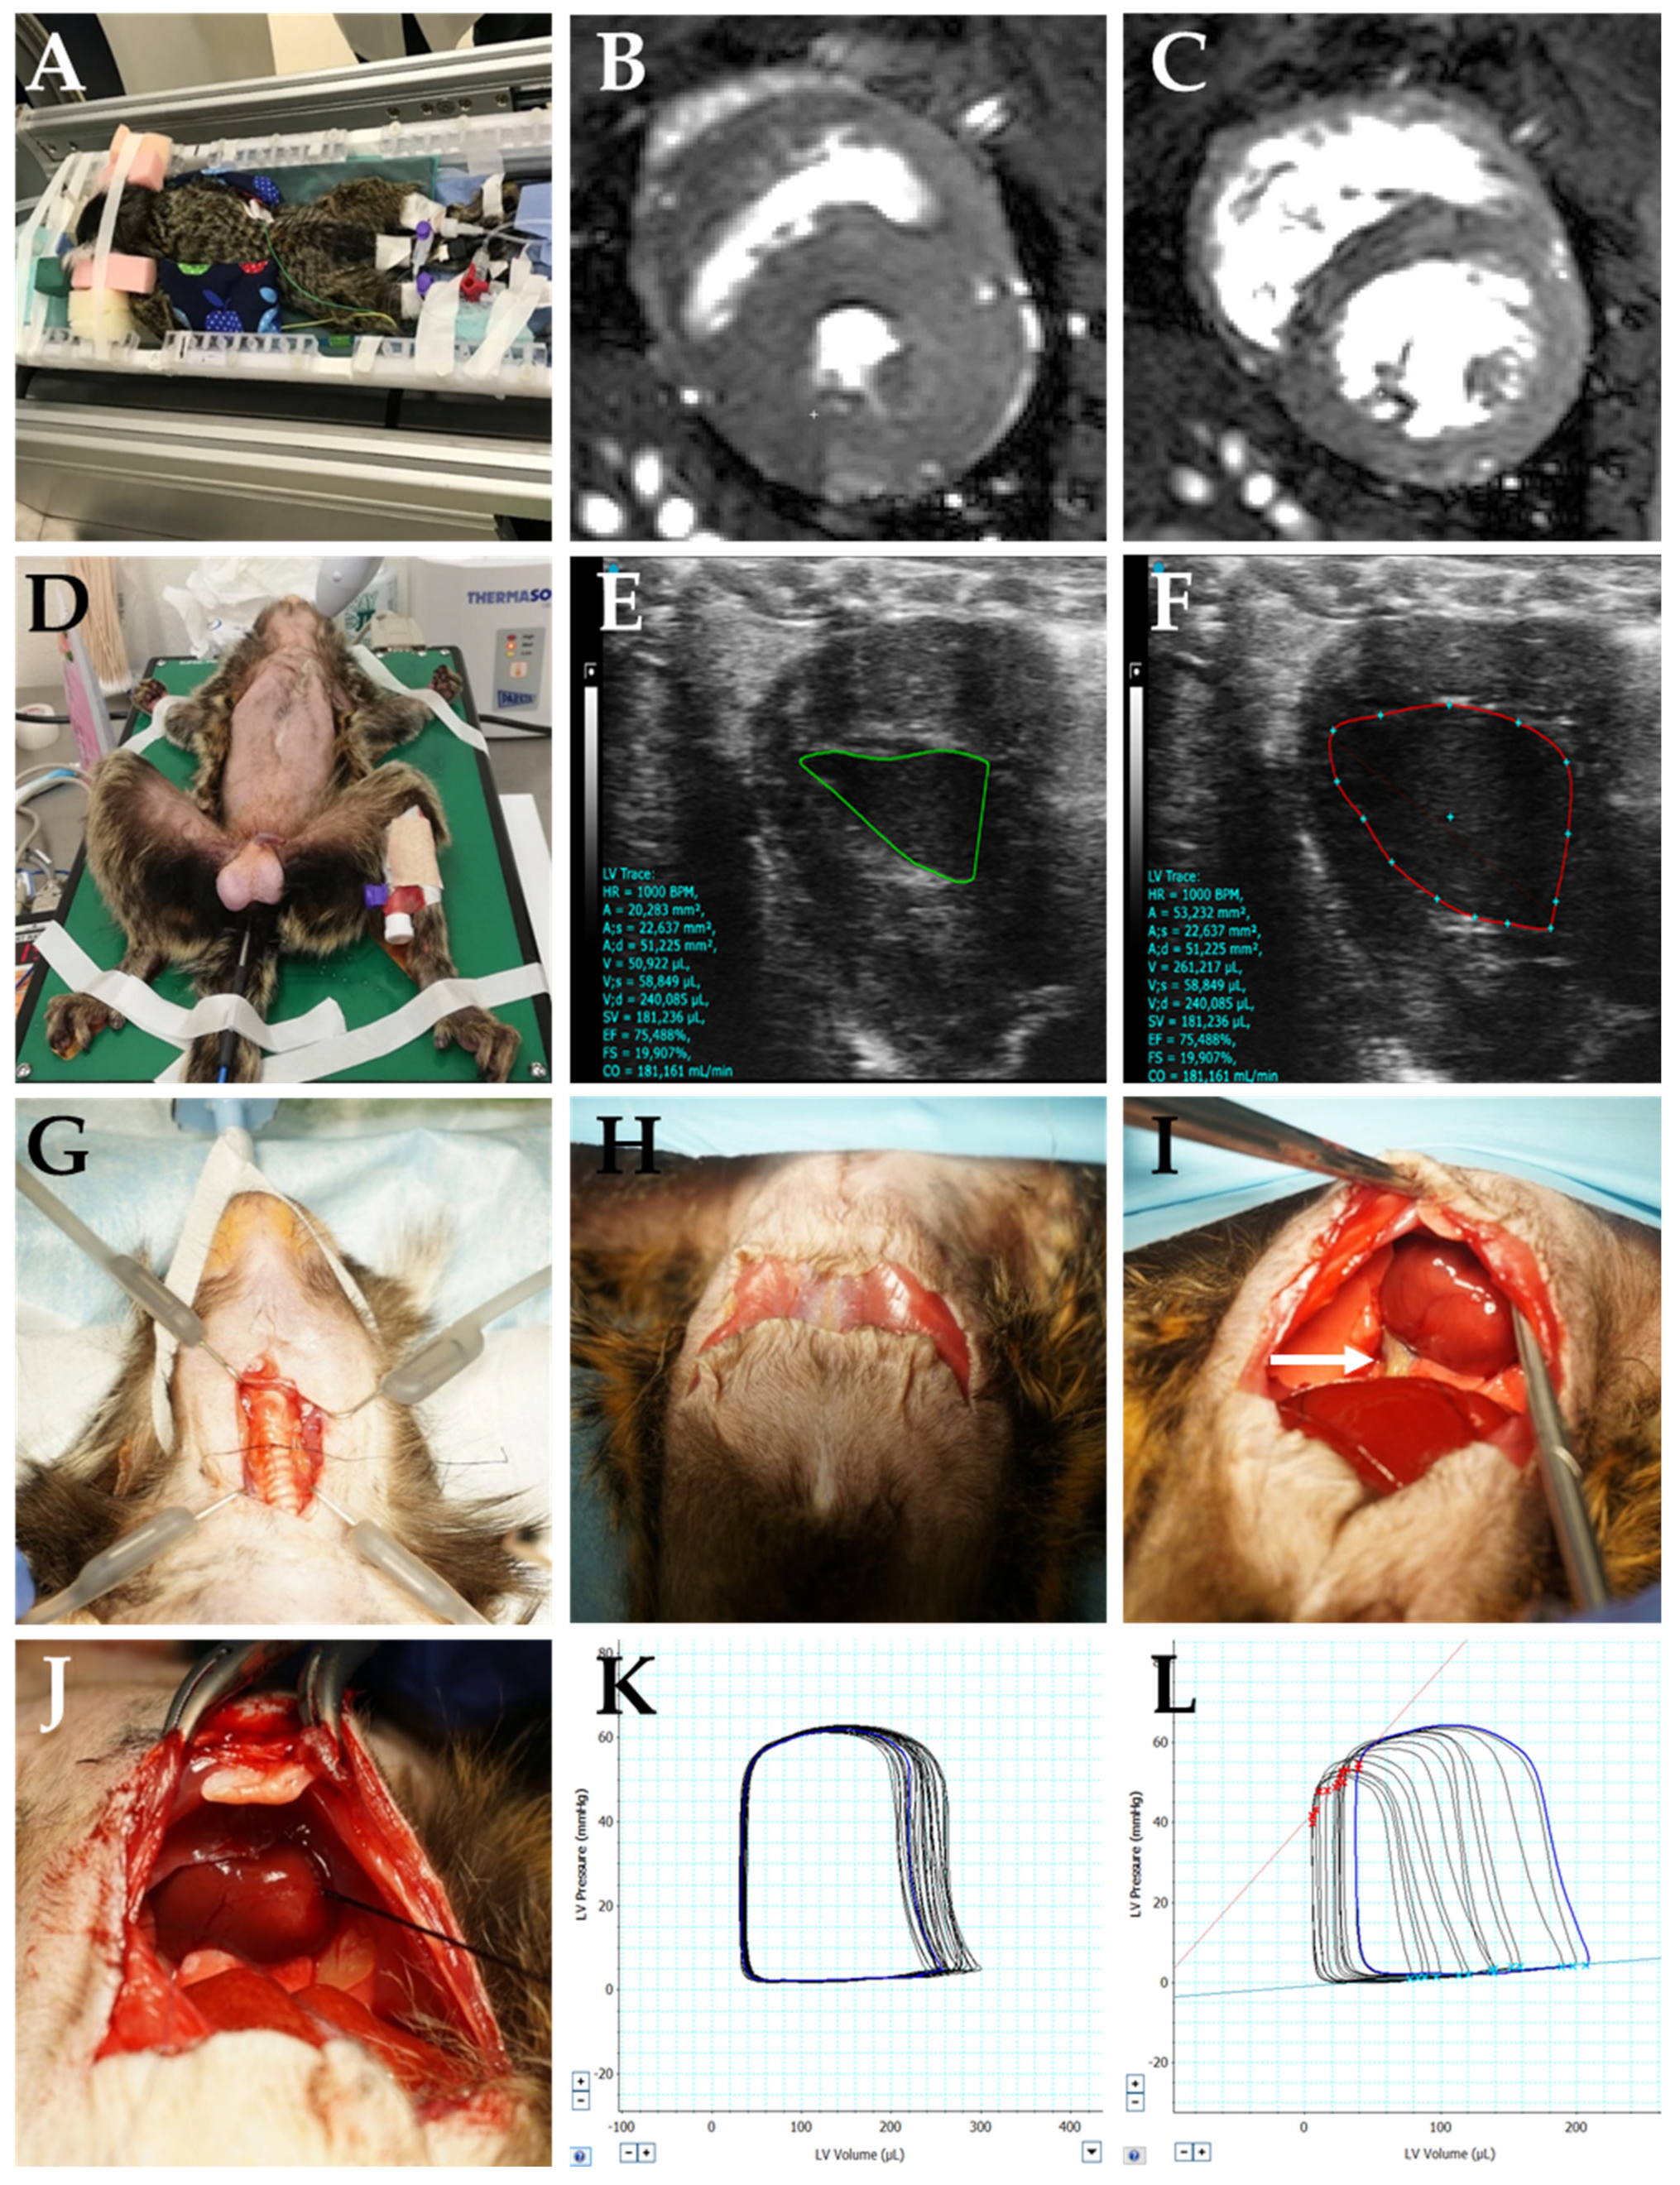

2.4. MRI

2.5. Echocardiography

2.6. PV Loop Measurement

2.6.1. Surgery for Hemodynamic Measurement Intervention

2.6.2. Hemodynamic Measurement

3.1. PV Loop Measurements

3.3. Echocardiographic Measurements